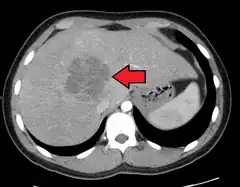

![]() Absceso hepático en la imagen axial de TAC: una lesión hipodensa en el hígado con realce periférico. | ||

En el ultrasonido se mostrará una masa quística en el hígado que tiende a ser septado o bien con características homogéneas. Si se hace una tomografía axial computarizada (TAC), se apreciará una masa hipodensa (oscura) con bordes precisos.[10] La aspiración percutánea del absceso y su cultivo microbiológico es esencial para el tratamiento adecuado y el drenaje del absceso. Con frecuencia se instala un catéter de drenaje, en especial para pacientes con abscesos complejos o que contengan fluido muy espeso. Los abscesos múltiples son comunes en pacientes inmunosuprimidos y se debe considerar varios organismos etiológicos, incluyendo una candidiasis.